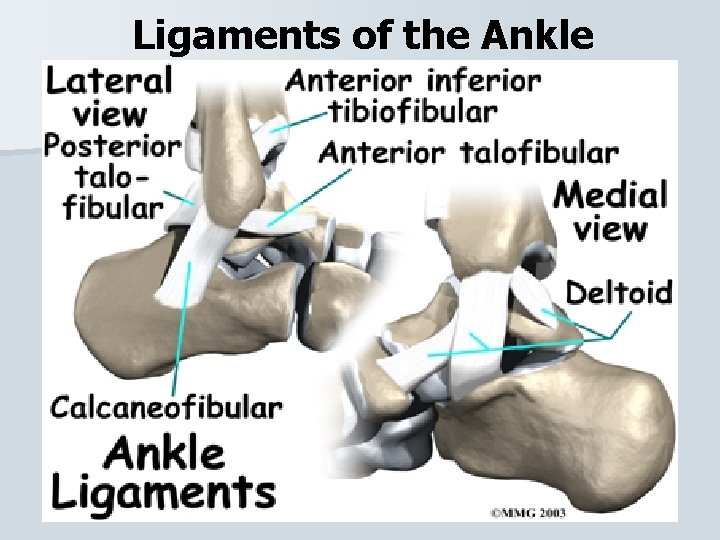

Ligaments of the Ankle

Ligaments of the Ankle

Ligament Injuries Lateral and Medial Ankle Sprain Majority of ankle sprains occur Inversion (85%) where Eversion (15%). • When the ankle inverts the lateral ligament are injured (ATF and calcaneofibular) and when it everts the medial ligamant (deltoid) is injured. •

Ligament Injuries Syndesmosis – another type of ankle sprain that is a high ankle sprain injures the syndesmosis that binds the tibia and fibula together. When the ankle is either severely, everted or rotated, the talus can force the tibia and fibula to spread apart. Syndesmotic sprains take longer to heal.